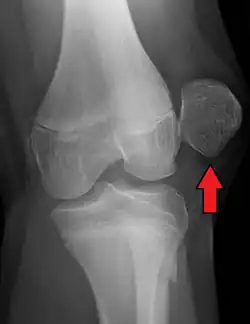

![]() | |

| X-ray showing a patellar dislocation, with the patella out to the side. | |

A patellar dislocation typically occurs when the knee is straight and the lower leg is bent outwards when twisting.[1][2] Occasionally, it occurs when the knee is bent and the patella is struck directly.[1] Commonly associated sports include soccer, gymnastics, and ice hockey.[2] Dislocations nearly always occur away from the midline.[2] Diagnosis is typically based on symptoms and supported by X-rays.[2]

On X-ray, with skyline projections, dislocations are readily diagnosed. In borderline cases of subluxation, the following measurements can be helpful: